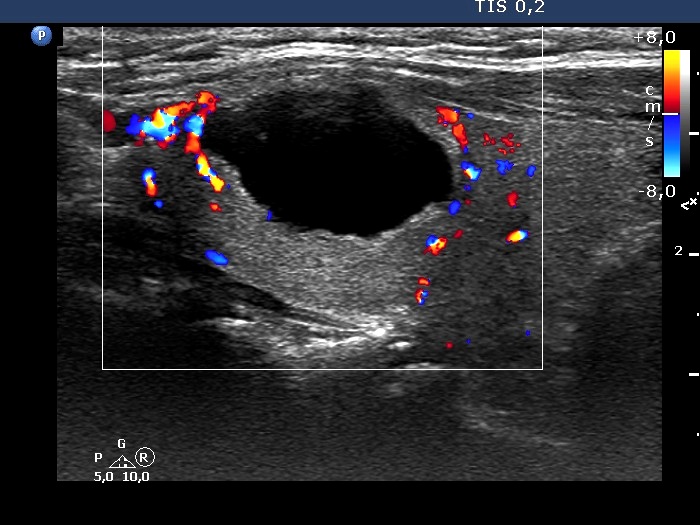

Left lobe, longitudinal scan, color Doppler mode. The lesion has perinodular blood flow.